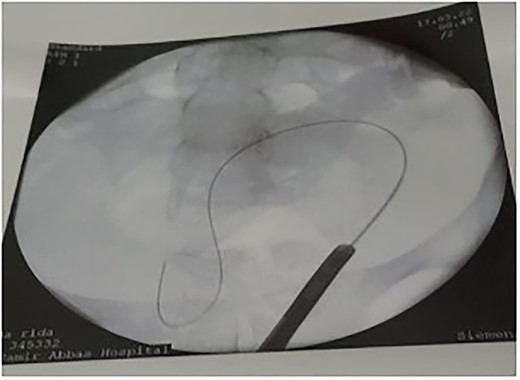

The patient tolerated the procedure very well and was transferred to the recovery room in stable condition. We did inform the patient that there is a small likelihood of developing a fistula within 2 weeks post-operatively. The patient did well in the post-operative period, recovered and was discharged to home in a stable condition. Unfortunately, on day 8, post-operatively, she started to have a leakage of urine per vagina. She was admitted for investigation, a CT Urogram was done with delayed images that confirmed the diagnosis of ureterovaginal fistula. The urologist was involved and consulted at this point; the plan was to take the patient for cystoscopy with retrograde ureteroscopy. Ureteroscopy wth retrograde fluoroscopy showed evidence of a ureterovaginal fistula (Figs 4 and 5) in which a DJ stent was inserted successfully (Fig. 6). The patient was explained about the post-operative course and plan. We decided to keep the stent for 12 weeks and then re-assess. The patient was covered by prophylaxis low-dose nitrofurantoin single daily dose of 100 mg. Fortunately, the leakage decreased gradually until it stopped. The patient was taken to the operating room to re-assess the fistula by cystoscopy and retrograde fluoroscopy. Retrograde fluoroscopy confirmed that the fistula healed. The stent was removed, and the patient was discharged to home in a stable condition.